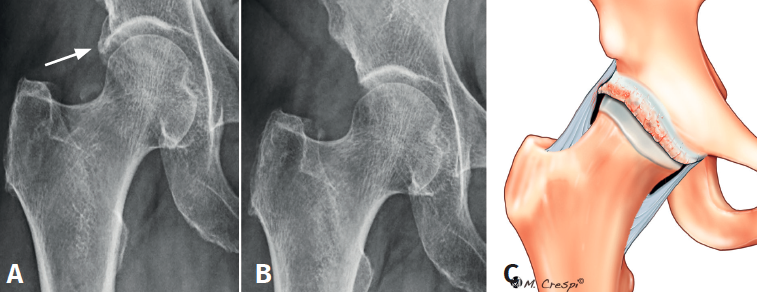

Tipo D: combinación de A y B, labrum acetabular y porción directa del recto anterior. Osificación del borde periacetabular de doble capa

- Características y morfología radiográfica: recientemente ha sido publicado un caso de doble calcificación combinada de labrum de tipo os acetabuli (A2) asociada a una calcificación difusa de porción directa de recto anterior (B3)(3)(Figura 9).

- Localización y lesiones asociadas: en la zona periacetabular y en la porción directa del recto anterior, con asociación de rotura labral y deformidad de tipo cam.

- Tratamiento: extirpación regional siguiendo las directrices ya mencionadas en los casos anteriores, incluyendo la reparación labral y la osteocondroplastia.